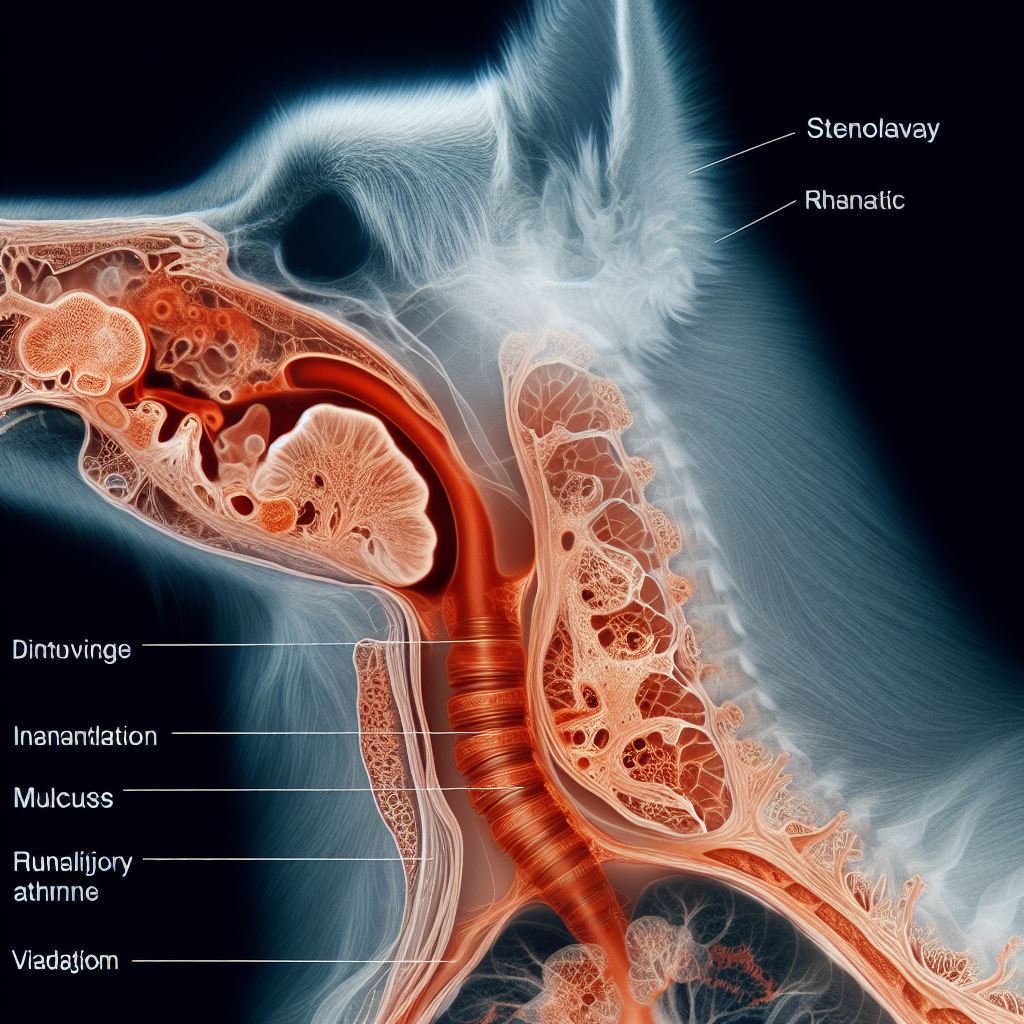

강아지 기관지 협착증 원인과 증상, 치료 방법 알아보기 사진

강아지 기관지 협착증 증상

기침

강아지가 지속적인 기침을 보이면 기관지 협착증의 가능성이 있습니다. 기침은 기관지 협착으로 인해 호흡 과정에서 발생하는 자극에 대한 반응으로 나타날 수 있습니다. 기침은 가벼운 경우부터 심하고 지속적인 경우까지 다양하게 나타날 수 있으며, 가끔씩 기침을 하는 경우부터 매우 자주 기침을 하는 경우까지 다양한 형태로 나타납니다.

호흡곤란

호흡에 어려움을 겪는 강아지는 기관지 협착증 증상일 수 있습니다. 강아지가 숨을 쉬는 것에 어려움을 겪는다면, 호흡곤란이라고 볼 수 있습니다. 호흡곤란은 가벼운 경우에는 숨소리나 숨결 간헐적인 문제로 나타날 수 있고, 심한 경우에는 호흡 속도가 빨라지고 숨을 쉬는데 애를 쓰는 모습을 보일 수 있습니다.

운동 시 호흡 문제

운동 중에 호흡에 어려움을 겪는 경우, 기관지 협착증이 의심됩니다. 강아지가 활동을 하거나 운동을 할 때, 호흡 속도가 빨라지고 숨을 쉬는데 어려움을 겪는다면, 기관지 협착증이 원인일 수 있습니다. 운동 시 호흡 문제는 강아지가 활발한 활동을 할 때 특히 두드러질 수 있으며, 이는 기관지 협착으로 인해 호흡 과정에서 발생하는 자극에 대한 반응입니다.

식욕 부진 및 체중 감소

강아지 기관지 협착증의 증상에 따라 식욕이 감소하고 체중이 감소할 수 있습니다. 증상으로 인해 호흡에 어려움을 겪는 강아지는 식욕이 줄어들 수 있습니다. 호흡 과정에서 소모되는 에너지가 증가하고 호흡이 힘들어지기 때문에 음식에 대한 관심과 식욕이 감소할 수 있으며, 이는 체중 감소로 이어질 수 있습니다.

증상 식별을 위한 주의사항

주인은 강아지의 특이한 행동이나 증상을 주의 깊게 관찰해야 합니다. 강아지의 기관지 협착증은 다양한 증상을 보일 수 있으며, 이를 식별하기 위해 주인은 강아지의 행동, 호흡, 식욕 등을 주의 깊게 관찰해야 합니다. 증상이 지속되거나 악화되는 경우, 가능한 빨리 수의사를 찾아 상담하는 것이 중요합니다.